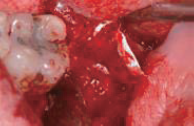

Stich- out after 2 weeks

Re- entry surgery after 7 month